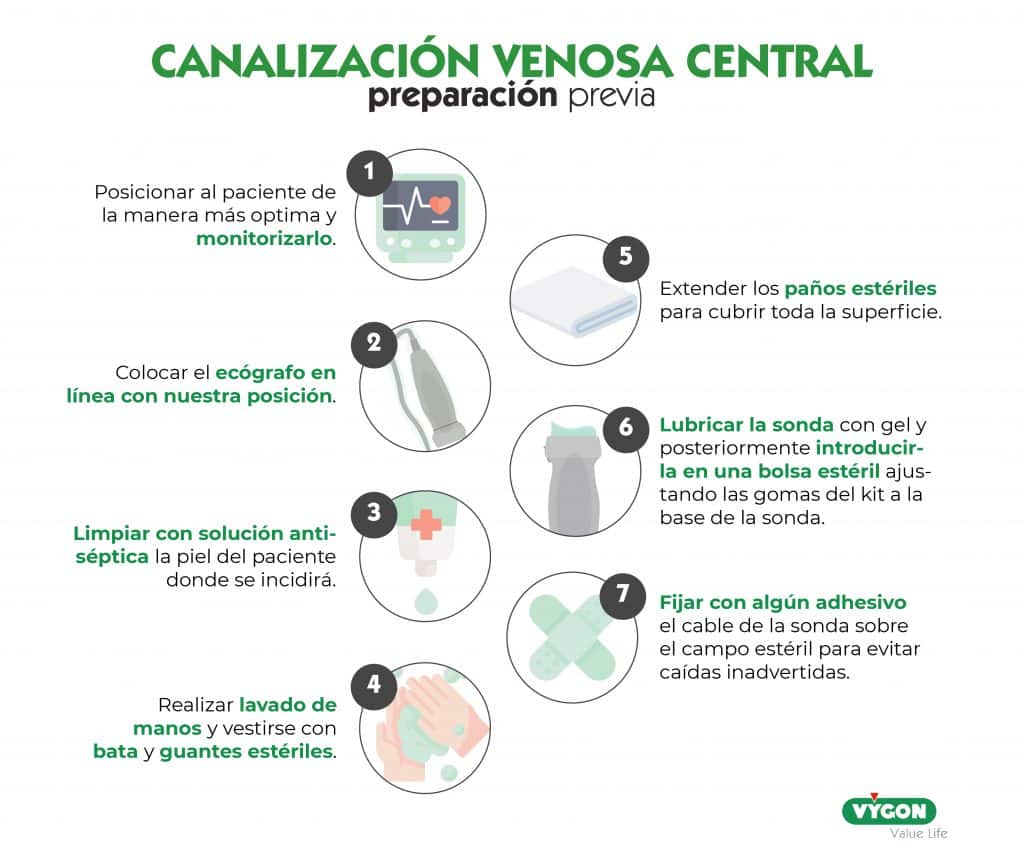

Montaje del campo estéril

Una vez hemos decidido que vena canalizar es el momento de preparar el lugar del trabajo y al paciente.

- Posicionaremos al paciente de la manera más optima y le monitorizaremos. Dado que estamos ante población pediátrica, esta técnica suele realizarse bajo anestesia general o sedación inh.

- Colocaremos el ecógrafo en línea con nuestra posición, tal y como se explicó en epígrafes anteriores.

- Limpiaremos con solución antiséptica la piel del paciente donde se incidirá.

- Realizaremos un lavado de manos y nos vestiremos con bata y guantes estériles.

- Extenderemos los paños estériles para cubrir toda la superficie.

- Con ayuda de otra persona cubriremos la sonda ecográfica con una funda estéril. Previamente lubricaremos la sonda con gel (estéril o no depende de la ayuda con la que contemos) y posteriormente la introduciremos en la bolsa estéril ajustando las gomas del kit a la base de la sonda.

- En última instancia fijaremos con algún adhesivo el cable de la sonda sobre el campo estéril para evitar caídas inadvertidas.